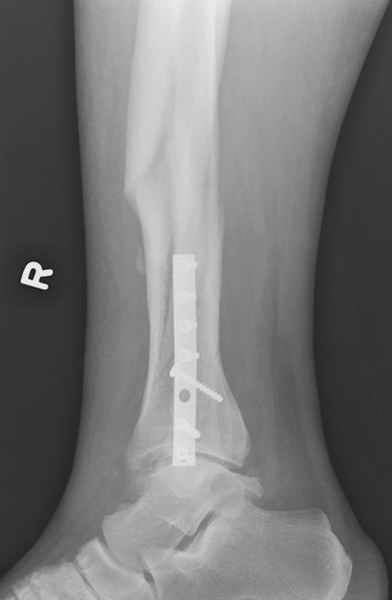

спрашивает что делать с больным который поступил недавно, фермер 55 лет падение при пьяной драке в баре, года два назад перенес операцию на лодыжке, на снимках и КТ перелом без вовлечения сустава,

Повреждение такой локализации, на которой применимы и аппарат (классический Илизарова или гибридный), пластина, особенно Locked Plate, и гвоздь с блокированием. В нашей клинике был бы выполнен закрытый интрамедуллярный остеосинтез. Желательно использовать гвоздь с возможностью провести более чем 2 обычных фронтальных винта в дистальном отломке.

Здесь мы использовали новый Synthes Nail с дополнительными дырками, в проксимальной части 4: по две косых и поперечные (один стандартный а другой динамический), в дистальной части две поперечные, прямая и косая. Вес больного более 120 кг, нагрузку начнем через месяц.

Получилось красиво, поздравляю. Вверху можно было ограничиться одним винтом во фронтальное статическое отверстие, зачем два 45-градусных?

При такий спирали задний край tibia может быть сломан - нет ли этого в данном случае? На всякий случай можно было ввести 1-2 винта 4,5 мм спереди назад мимо гвоздя. Хотя самый дистальный блокирующий винт, возможно, зацепил этот отломок. А какой тут диаметр гвоздя и locking винтов?